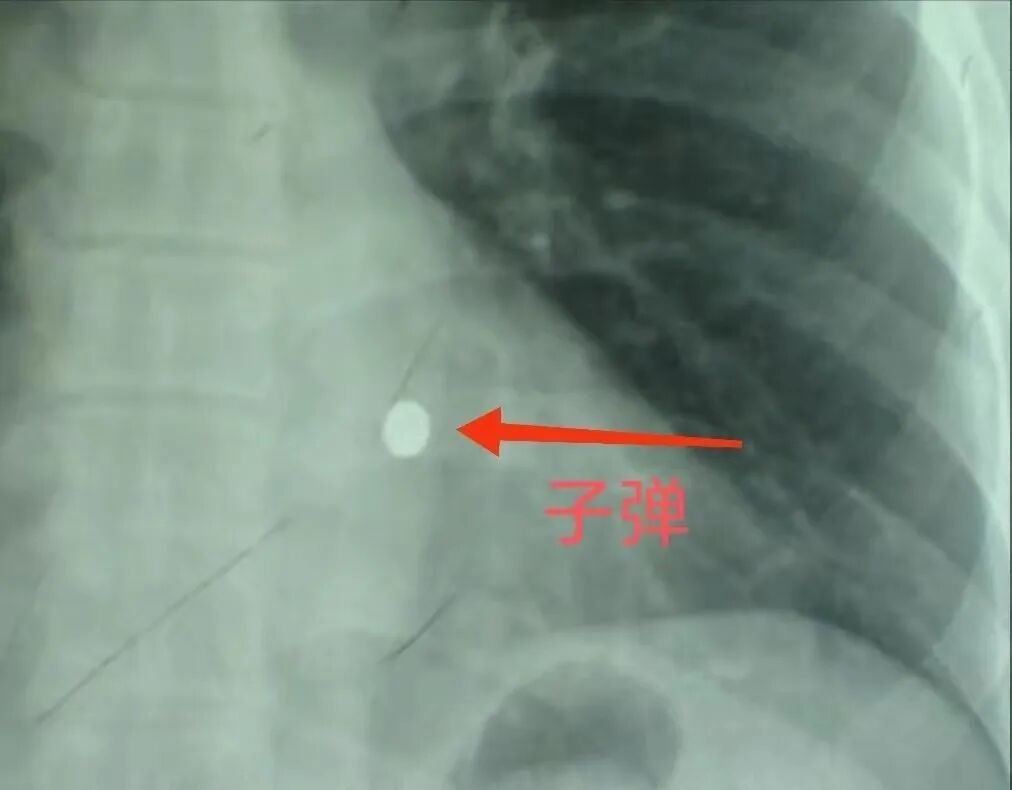

医生给他做了一个X光片,结果出来后发现片子上有一个金属状的白色圆点。

这次他脱掉了衣服,医生还给他做了一个侧方位的X光片,结果却让大家大吃一惊。

脱掉了衣服,片子上依旧出现了一颗白色圆点,而侧方位的片子上可以明显看出这是一颗子弹。

子弹甚至还随着心脏跳动。

但结果却让他大失所望,CT扫描以后可以明显看出,子弹已经深深嵌入了符桂林的心脏,随时都有可能要了他的命。